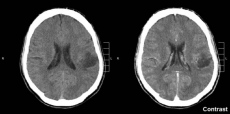

![[Img #48555]](upload/img/periodico/img_48555.jpg)

Marcadores de la infección presentes en la sangre de afectados permitieron que científicos de Brasil expliquen la senda de señalización celular que actúa tanto en la defesa inmunitaria como en la formación de neuronas. (Foto: Frontiers in Microbiology)